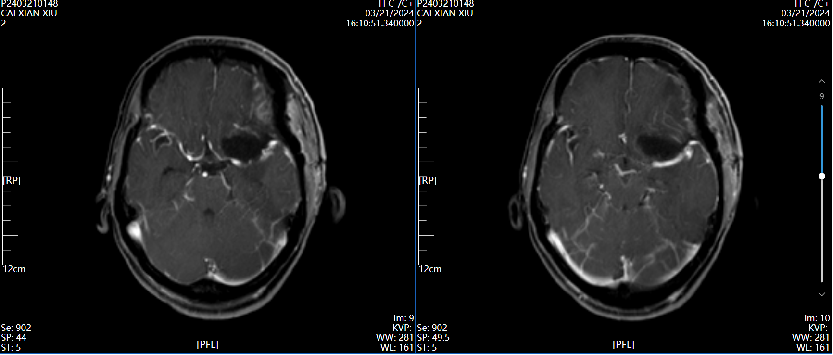

4、辅助检查:头颅磁共振检查提示:左侧前床突占位,约2.8×2.4×2.0cm大小,T1呈等低信号,T2呈等高信号,增强病灶明显强化,宽基底与前颅窝底、前床突相连,看见脑膜尾征。

术后第3天磁共振增强  2024.03.21